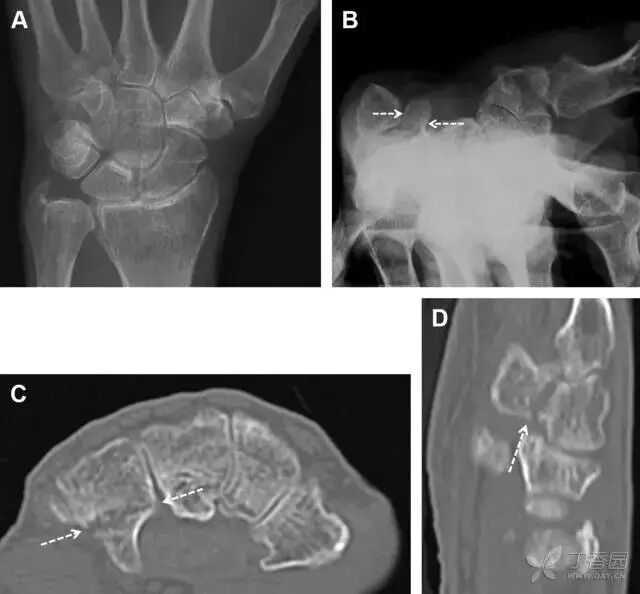

30桡骨远端骨折

常规进行前后位、侧位、斜位 X 线检查,对于大多数桡骨远端骨折来说不容易漏诊;但是对于无移位的骨折,特别是桡骨茎突骨折,容易漏诊。桡骨茎突骨折是一斜行的骨折,常累及关节面,常发生于轴向应力或直接打击。

图 1 57 岁女性,摔倒后手掌撑地,桡骨茎突压痛。(A~C)前后位、斜位、侧位片示软组织肿胀(*)和发丝样骨折(白色箭头);(D~F)2 周后,前后位、斜位、侧位片示骨折线显明,由于新骨痂沉积而呈现透亮线与硬化线并存;(G~I)另一患者,桡骨茎突骨折在前后位及侧位片上显示不明显,而在斜位片显示更清楚

31舟状骨骨折

舟状骨骨折 60%~70% 发生于腰部,15% 发生于近极, 10% 发生于远极, 8% 发生于远端关节面。除了常规的前后位、侧位、斜位片外,还需要拍专门的舟状骨位片(腕关节尺偏,以舟状骨为中心的腕关节前后位片),特别是鼻烟壶有压痛时。

图 2 舟状骨骨折 (A、B)第 1 例患者,舟状骨远极关节内骨折(白色箭头),斜位片显示较清楚(B);(C、D)第 2 例患者,舟状骨腰部骨折(虚线箭头),斜位片显示较清楚(D);(E~H)第 3 例患者,舟状骨近极骨折,常规 X 线片均未看到骨折,而在舟状骨位片上才能见到骨折(虚线圆)